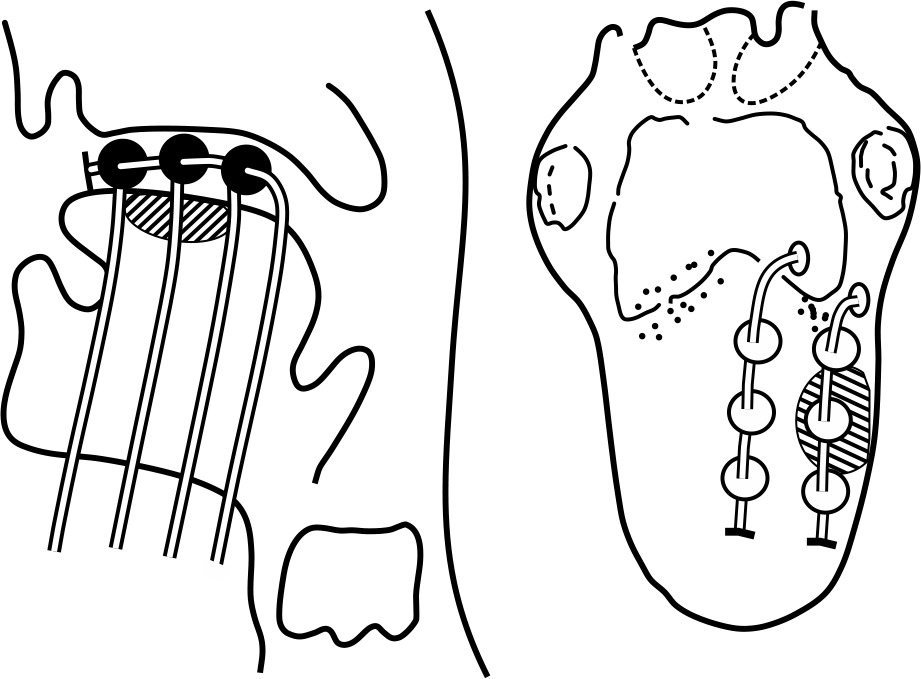

Isolate the thread (wound around the catheter underneath the bead/ball) of each line of the respective plane. Bind the threads of respective planes together. Now, club the bound threads of each plane and strap them together, and secure all of them on the side of the face without producing strain on catheters. Diagrammatic representation of the technique has been shown in Figure 2.

In a case of oral tongue lesions, lateral edge and upper/superior surface are beneficial to under-dose. The upper or superior surface underdose can be resolved by using Bhalavat’s T ball/bead technique. Lateral edge underdose, whenever required, can be settled by separate catheter or differential distance (between lines/planes nearer to shorter edge), compared to the one on opposite/away side or differential loading/unloading of activity, or time which is expected to solve underdosage to some extent. Skin and subcutaneous dose is avoided or limited [20] (Figure 4).